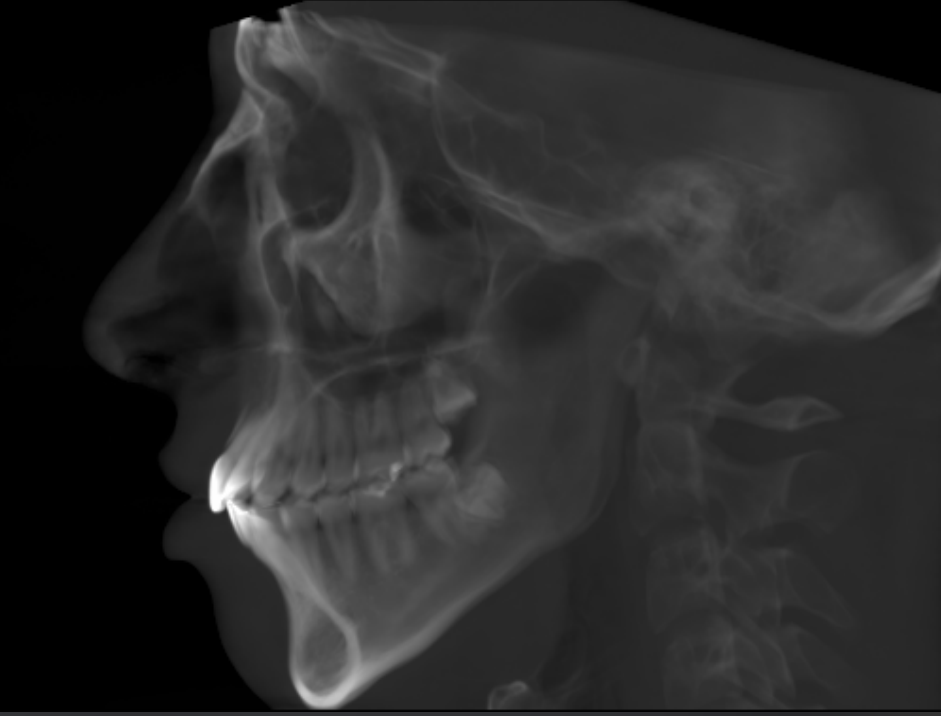

At least 4* of counter clockwise rotation on both jaws.

5mm+ advancement on both maxilla and mandible

7mm+ genioplasty

My jaw surgery movements are limited because of my natural unfortunate teeth position and a combination of other factors.

I have what some asian surgeons describe as a “protruding mouth.” However that type of protrusion is often related to the shape of the maxilla and is typically addressed by removing a portion of the maxilla, often together with tooth extractions which is very fucking dumb.

After jaw surgery my face may actually look somewhat worse initially because the “protruding mouth” could become more noticeable.

That’s why my top priority is getting a custom premaxillary implant to balance my midface with the jaw.

At least 4* of counter clockwise rotation on both jaws.

5mm+ advancement on both maxilla and mandible

7mm+ genioplasty

My jaw surgery movements are limited because of my natural unfortunate teeth position and a combination of other factors.

I have what some asian surgeons describe as a “protruding mouth.” However that type of protrusion is often related to the shape of the maxilla and is typically addressed by removing a portion of the maxilla, often together with tooth extractions which is very fucking dumb.

After jaw surgery my face may actually look somewhat worse initially because the “protruding mouth” could become more noticeable.

That’s why my top priority is getting a custom premaxillary implant to balance my midface with the jaw.